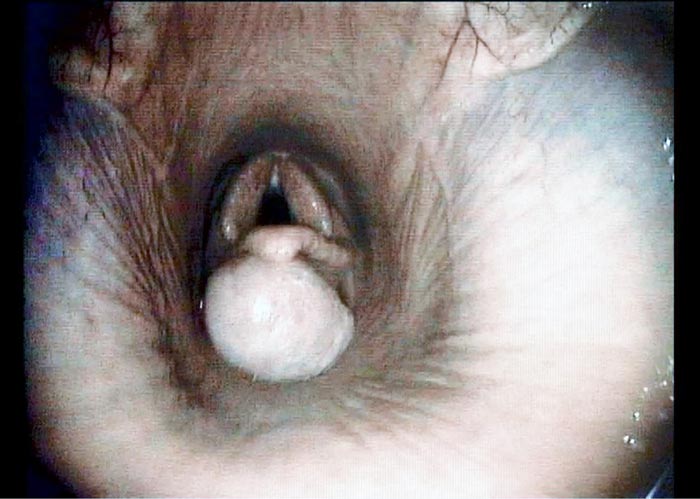

A transendoscopic lance was used to penetrate the cyst and aspirate approximately 15ml of serous fluid (Figure 2). This partially deflated the cyst, easing manipulation and assisting in dissection. With endoscope in situ, curved bronchoesophageal grasping forceps were passed through the contralateral nasal passage and used to manipulate the cyst (Figure 3). A transendoscopic diode laser was used to excise the cyst en bloc, along with the overlying subepiglottic mucosa using a contact technique (Figures 4 and 5). Following excision, topical dexamethasone sodium phosphate (total 20mg) was applied to the surgical site.